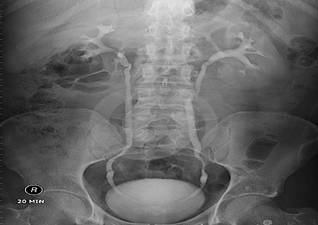

幸好我们有B超、X线造影、CT三维成像这三*法大**宝,任何结石都在这“照妖镜”前都无所遁形。

Tips:其中B超简单、无创,可以用来初步筛查,但由于受到腹部肠气干扰,针对没有扩张积水的输尿管及结石显影模糊不清,并且受到检查设备及检查医师的经验水平限制。X线造影可以直观的将结石的剪影投射在一张平片上,就像平常我们照相般反应结石及肾脏集合系统的大致情况。B超、X线造影的缺陷在于,其影像都是二维平面,看到结石也仅仅是一个片面,CT三维成像则能提供一个三维立体的图像,将肾脏及其中的结石直观立体地显现在我们面前。这三者针对医师评估病情,决定手术方式、手术入路具有非常重要的作用。这就是为什么我们需要给每个结石病人做多种检查的原因,因为它们各有优缺点,互相验证,互相弥补,通过完善的检查,可以让患者结石的位置和形态在主刀医生的大脑中清晰的显现!

X线造影